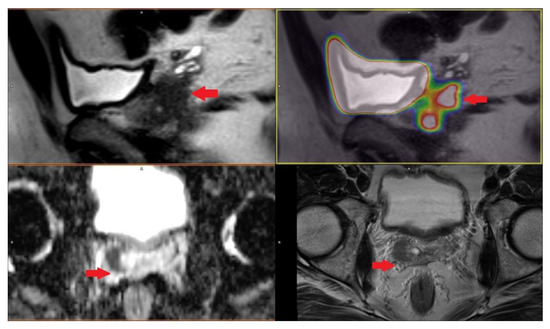

PET/CT with radiolabeled choline analogs is widely used in clinical practice for prostate cancer staging. 18F-fluoroethylcholine PET demonstrated higher accuracy than MRI for the detection of primary prostate cancer; specificity was however limited by choline uptake in benign lesions [15]. Since 2012, [18F]- and [68Ga]-labeled inhibitors of prostate-specific membrane antigen (PSMA) entered early clinical development for PET imaging of PCa and showed immediate promise for sensitive and specific identification of local and distant sites of disease [16,17]. Results from [68Ga]-PSMA-11 PET/MRI and PET/CT in Figure 2, Figure 3 and Figure 4. To summarize, according to the available systematic reviews and clinical trials, the sensitivity and specificity in primary staging of PCa using PSMA ligands is usually above 40% and over 85%, respectively. The impact on therapy planning was also investigated, performing PET/CT or, less frequently, PET/MRI using PSMA ligands, the therapeutic procedure changes in approximately 21% of patients in the primary staging [18,19].

Figure 2. Patient with prostate cancer GS 7 (4 + 3) in right lobe with right seminal vesicle invasion cT3b iPSA 4.17 PHI 64.93 in [68Ga]-PSMA-11 PET/MRI.

Life 11 00324 g002